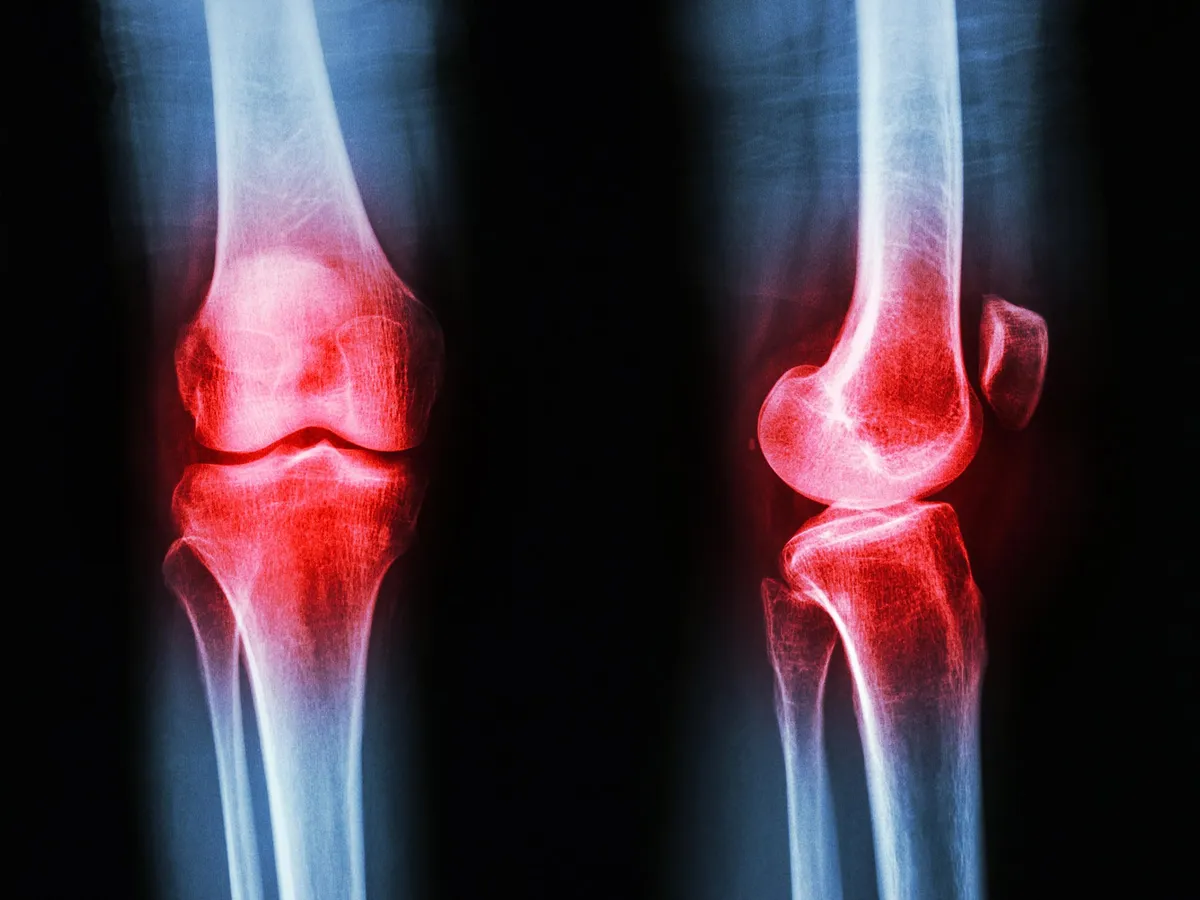

For years, the medical world has treated arthritis like an angry houseguest: you manage the symptoms, try to keep the peace, but never quite get to the root of what's making them so mad. Think pain meds and anti-inflammatories, essentially politely asking the joints to chill out.

Previous studies had hinted at GLP-1's anti-inflammatory properties, but actually finding it in the joint fluid of arthritis patients is a whole new ballgame. It gives scientists a solid reason to investigate whether these drugs could directly treat arthritis, moving beyond their known metabolic effects.